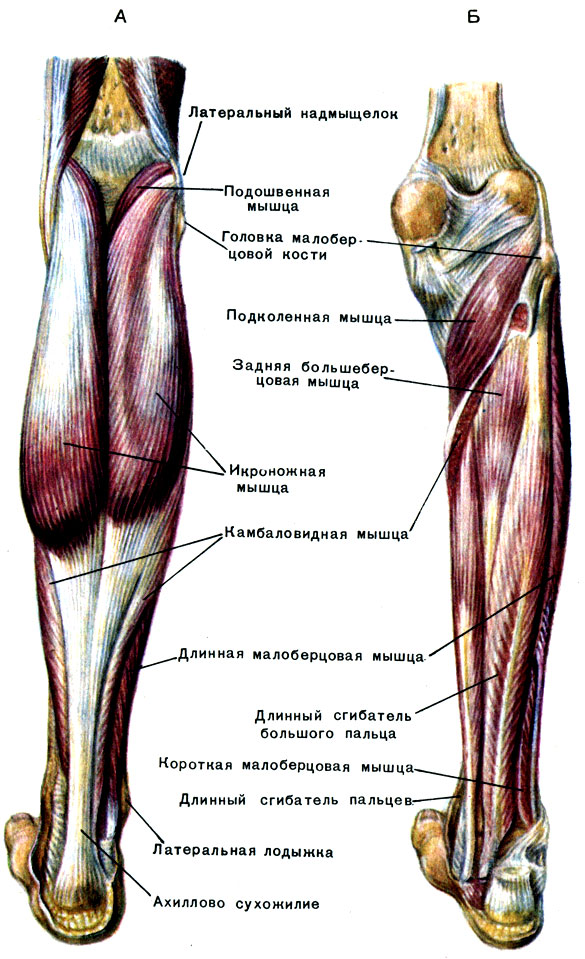

Анатомия подошвенной мышцы голени: подробное рассмотрение